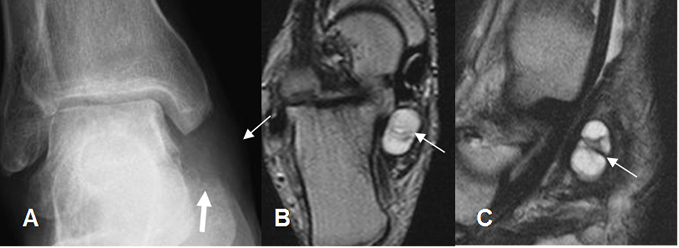

Fig 118 B. Síndrome del tarso.

A: Rx AP. Prominencia de tejidos blandos, por debajo del maléolo interno y que remodela en calcáneo. (Flecha gruesa).

B: RM axial y C: RM sagital en T2. Lesión ovalada, de consistencia líquida, en relación con el tendón del tibial posterior, que ocupa el seno del tarso y corresponde a ganglión.